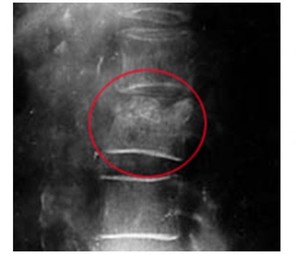

Межпозвоночная грыжа такого вида характеризуется тем, что на снимке того или иного отдела наблюдается деформация межпозвоночного диска. При всем этот, сам диск никак не смещается. К тому же это заболевание не влияет на нервные корешки и сам спинной мозг.

Чаще всего узлы позвоночника сопровождаются сильной болью в спине. В первую очередь пациента отправляют на рентгеновский снимок. Заболевание Шморля характеризуется вертикальными светлыми полосами, которые легко заметить на фоне темного оттенка позвонка.